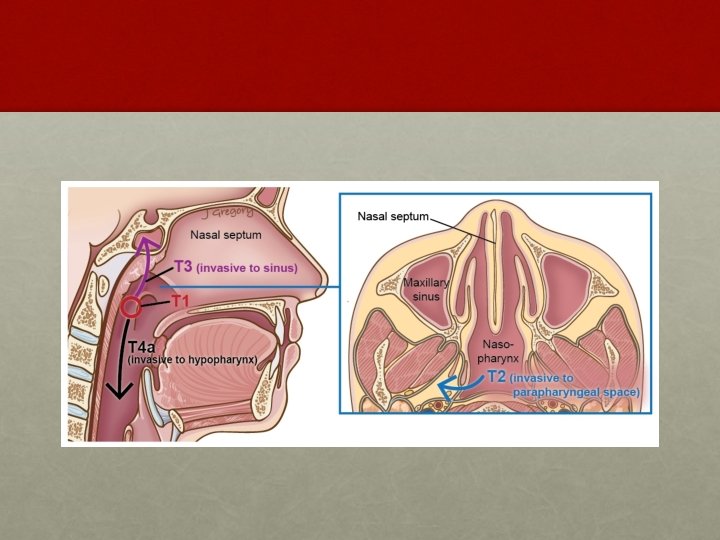

AJCC system: T staging • T 1: • Tumor confined to the nasopharynx • T 2: • Tumor extends to soft tissues • T 2 a : Extends to the oropharynx or the nasal fossa • T 2 b : With parapharyngeal extension • T 3: • Tumor invades bony structures and/or paranasal sinuses • T 4: • Tumor with intracranial extension and/or involvement of cranial nerves, infratemporal fossa, hypopharynx, orbit, or masticator space Department of Radiotherapy, PGIMER, Chandigarh